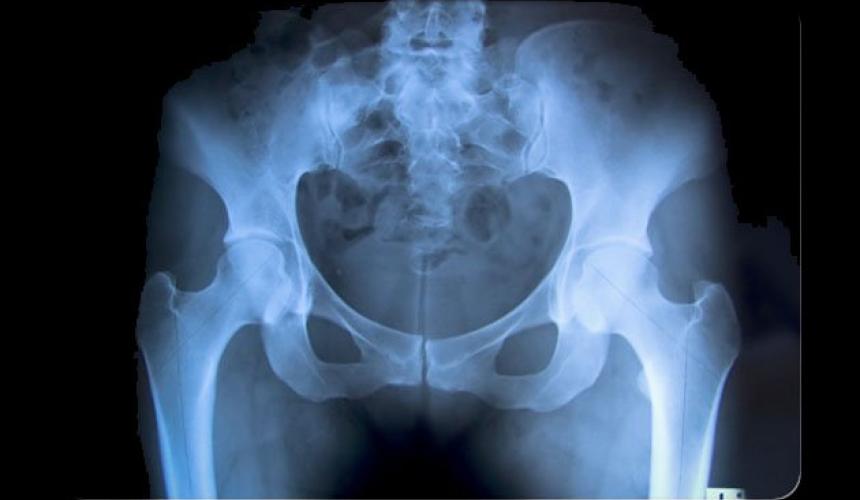

Οι γυναίκες που κάνουν φυτοφαγική διατροφή, έχουν 33% μεγαλύτερο κίνδυνο να πάθουν κάταγμα στο ισχίο (γοφό), σε σχέση με όσες τρώνε κρέας τακτικά (τουλάχιστον πέντε φορές την εβδομάδα), δείχνει μια νέα βρετανική επιστημονική έρευνα.

Οι ερευνητές του Πανεπιστημίου του Λιντς, με επικεφαλής τον Τζέιμς Γουέμπστερ, οι οποίοι έκαναν τη σχετική δημοσίευση στο ιατρικό περιοδικό «BMC Medicine», ανέλυσαν στοιχεία για 26.318 γυναίκες ηλικίας 35 έως 69 ετών, από τις οποίες οι 822 (σχεδόν το 3%) είχαν πάθει κάταγμα ισχίου στη διάρκεια περίπου 22 ετών.

Αφού ελήφθησαν υπόψη άλλοι παράγοντες όπως το κάπνισμα, βρέθηκε ότι οι φυτοφάγες γυναίκες ήταν η ομάδα με τον πιο αυξημένο κίνδυνο για το εν λόγω κάταγμα. Οι επιστήμονες τόνισαν την ανάγκη το ζήτημα να μελετηθεί περαιτέρω, ώστε να εξηγηθούν καλύτερα οι ακριβείς αιτίες που η φυτοφαγική διατροφή σχετίζεται με αυξημένο κίνδυνο κατάγματος του ισχίου.

Συνεπώς, σύμφωνα με τους ερευνητές, γίνεται όλο και πιο σημαντικό να μελετηθεί κατά πόσο η φυτοφαγική διατροφή μπορεί να αποτελέσει πρόβλημα δημόσιας υγείας όσον αφορά τα κατάγματα. Η καθηγήτρια Τζάνετ Κέιντ της Σχολής Επιστήμης της Διατροφής του Λιντς δήλωσε ότι «τα κατάγματα του ισχίου αποτελούν ήδη ένα παγκόσμιο πρόβλημα υγείας με σημαντικό οικονομικό κόστος, προκαλώντας απώλεια ανεξαρτησίας του ασθενούς, μείωση της ποιότητας ζωής του και αύξηση κινδύνου για άλλα προβλήματα υγείας. Η νέα μελέτη αποτελεί ένα σημαντικό βήμα για να κατανοηθεί καλύτερα ο δυνητικός κίνδυνος από τις φυτοφαγικές δίαιτες σε βάθος χρόνου και τι μπορεί να γίνει για να μετριαστούν αυτοί οι κίνδυνοι».